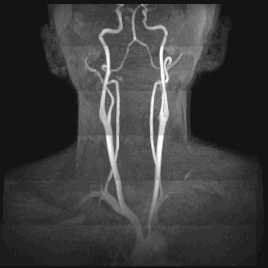

Процедура исследования при. МРТ головного мозга с ангиографией сосудов ничем не отличается от обычной. Пациент размещается в закрытой камере томографа в горизонтальном положении, где должен находиться в неподвижном состоянии около ти минут. В случае клаустрофобии или невозможности сохранить неподвижность вследствие определенных болезней или нервных патологий, он может вводиться в состояние медикаментозного сна наркоза. Разница с обычной томографией состоит в применении специальных компьютерных программ, настроенных на формирование изображения именно кровеносных сосудов мозга и шейного отдела. Важность диагностики сосудов шейного отдела в режиме ангиографии обусловлена тем, что это единственный путь поступления крови в область мозга. Нарушение этого русла приводит к очень тяжелым поражениям мозга. Особенно опасны аневризмы и тромбозы артерий и вен шейной области. Нарушение снабжения кровью мозгового отдела может быть вызвано и остеохонд розами шейного отдела.